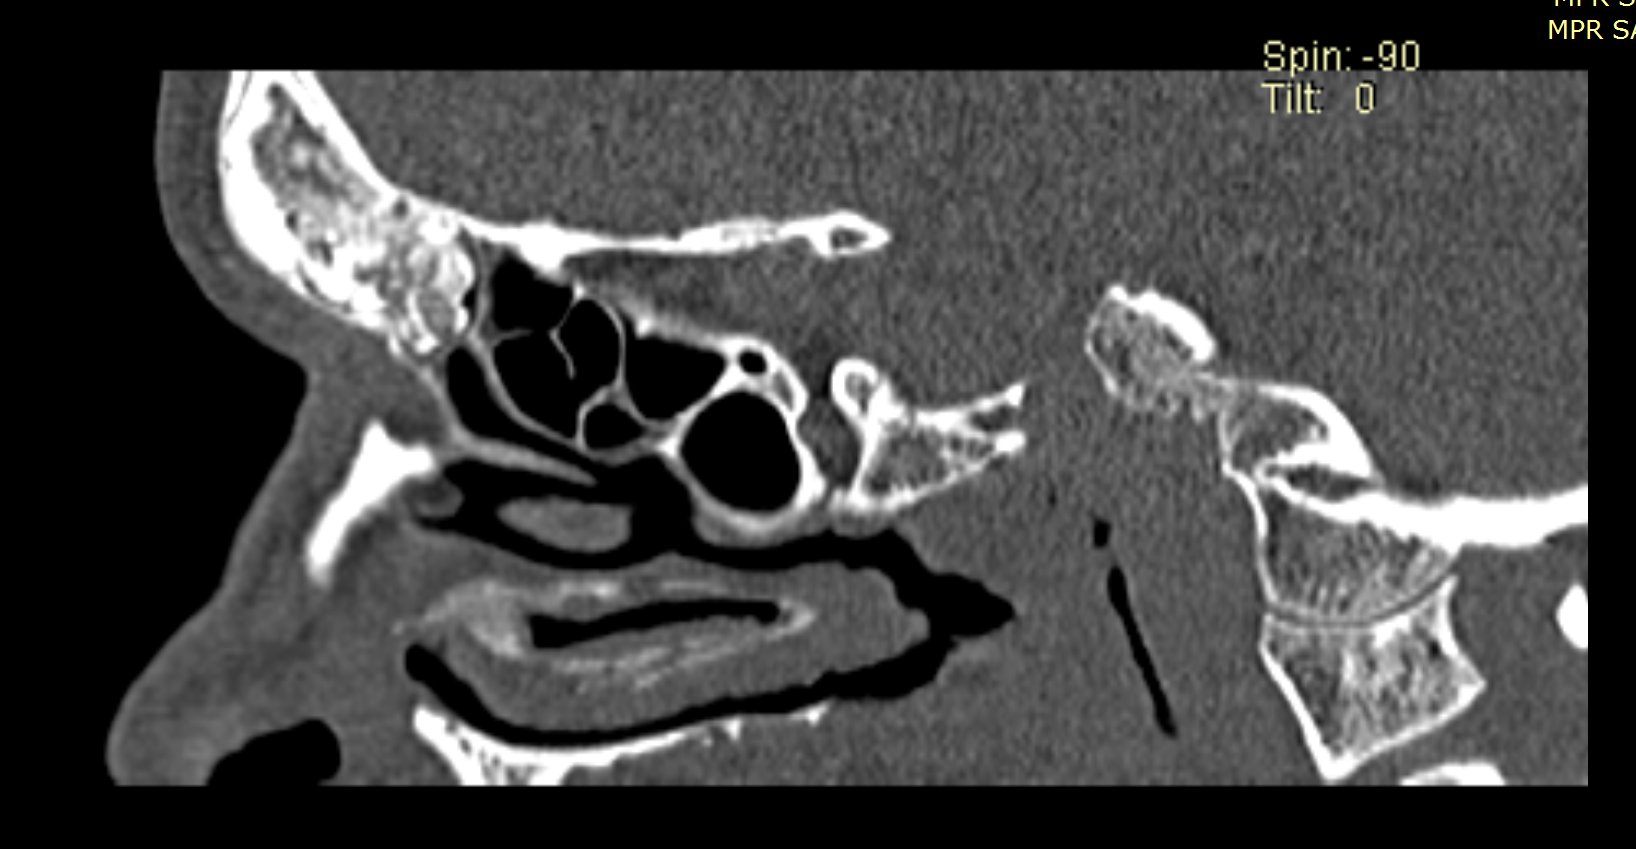

Examenul clinic ORL și examenele imagistice complementare (CT, RMN sinusuri paranazale) pun în evidență o formațiune tumorală osteogenică a sinusului frontal drept, protruzivă în unghiul supero-intern al orbitei, extinsă medial către sinusul frontal stâng.